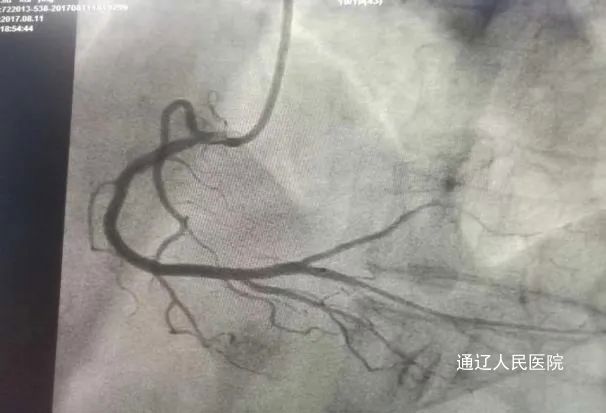

该患者曾在8个月前因“言语不利、左侧肢体活动不灵”的急性脑梗死入院治疗,行脑血管造影未见狭窄病变。不久后,患者又于1月余前因急性心梗入院,行冠脉造影未见明显狭窄病变。病情复杂,一连串的心脑血管事件却找不到原因,令医护团队倍感压力和挑战。

在心脑血管专家的会诊下,最终诊断为先天性心脏病-卵圆孔未闭。考虑该孔道是患者心梗、脑梗的罪魁祸首,在与患者及家属充分沟通后,决定于3月3日进行卵圆孔未闭封堵手术。手术过程顺利,仅用时20分钟便完成了手术,成功封堵了卵圆孔。在心内科医护团队的精心护理下,患者术后恢复良好,心脑疾病的威胁得到了有效控制。